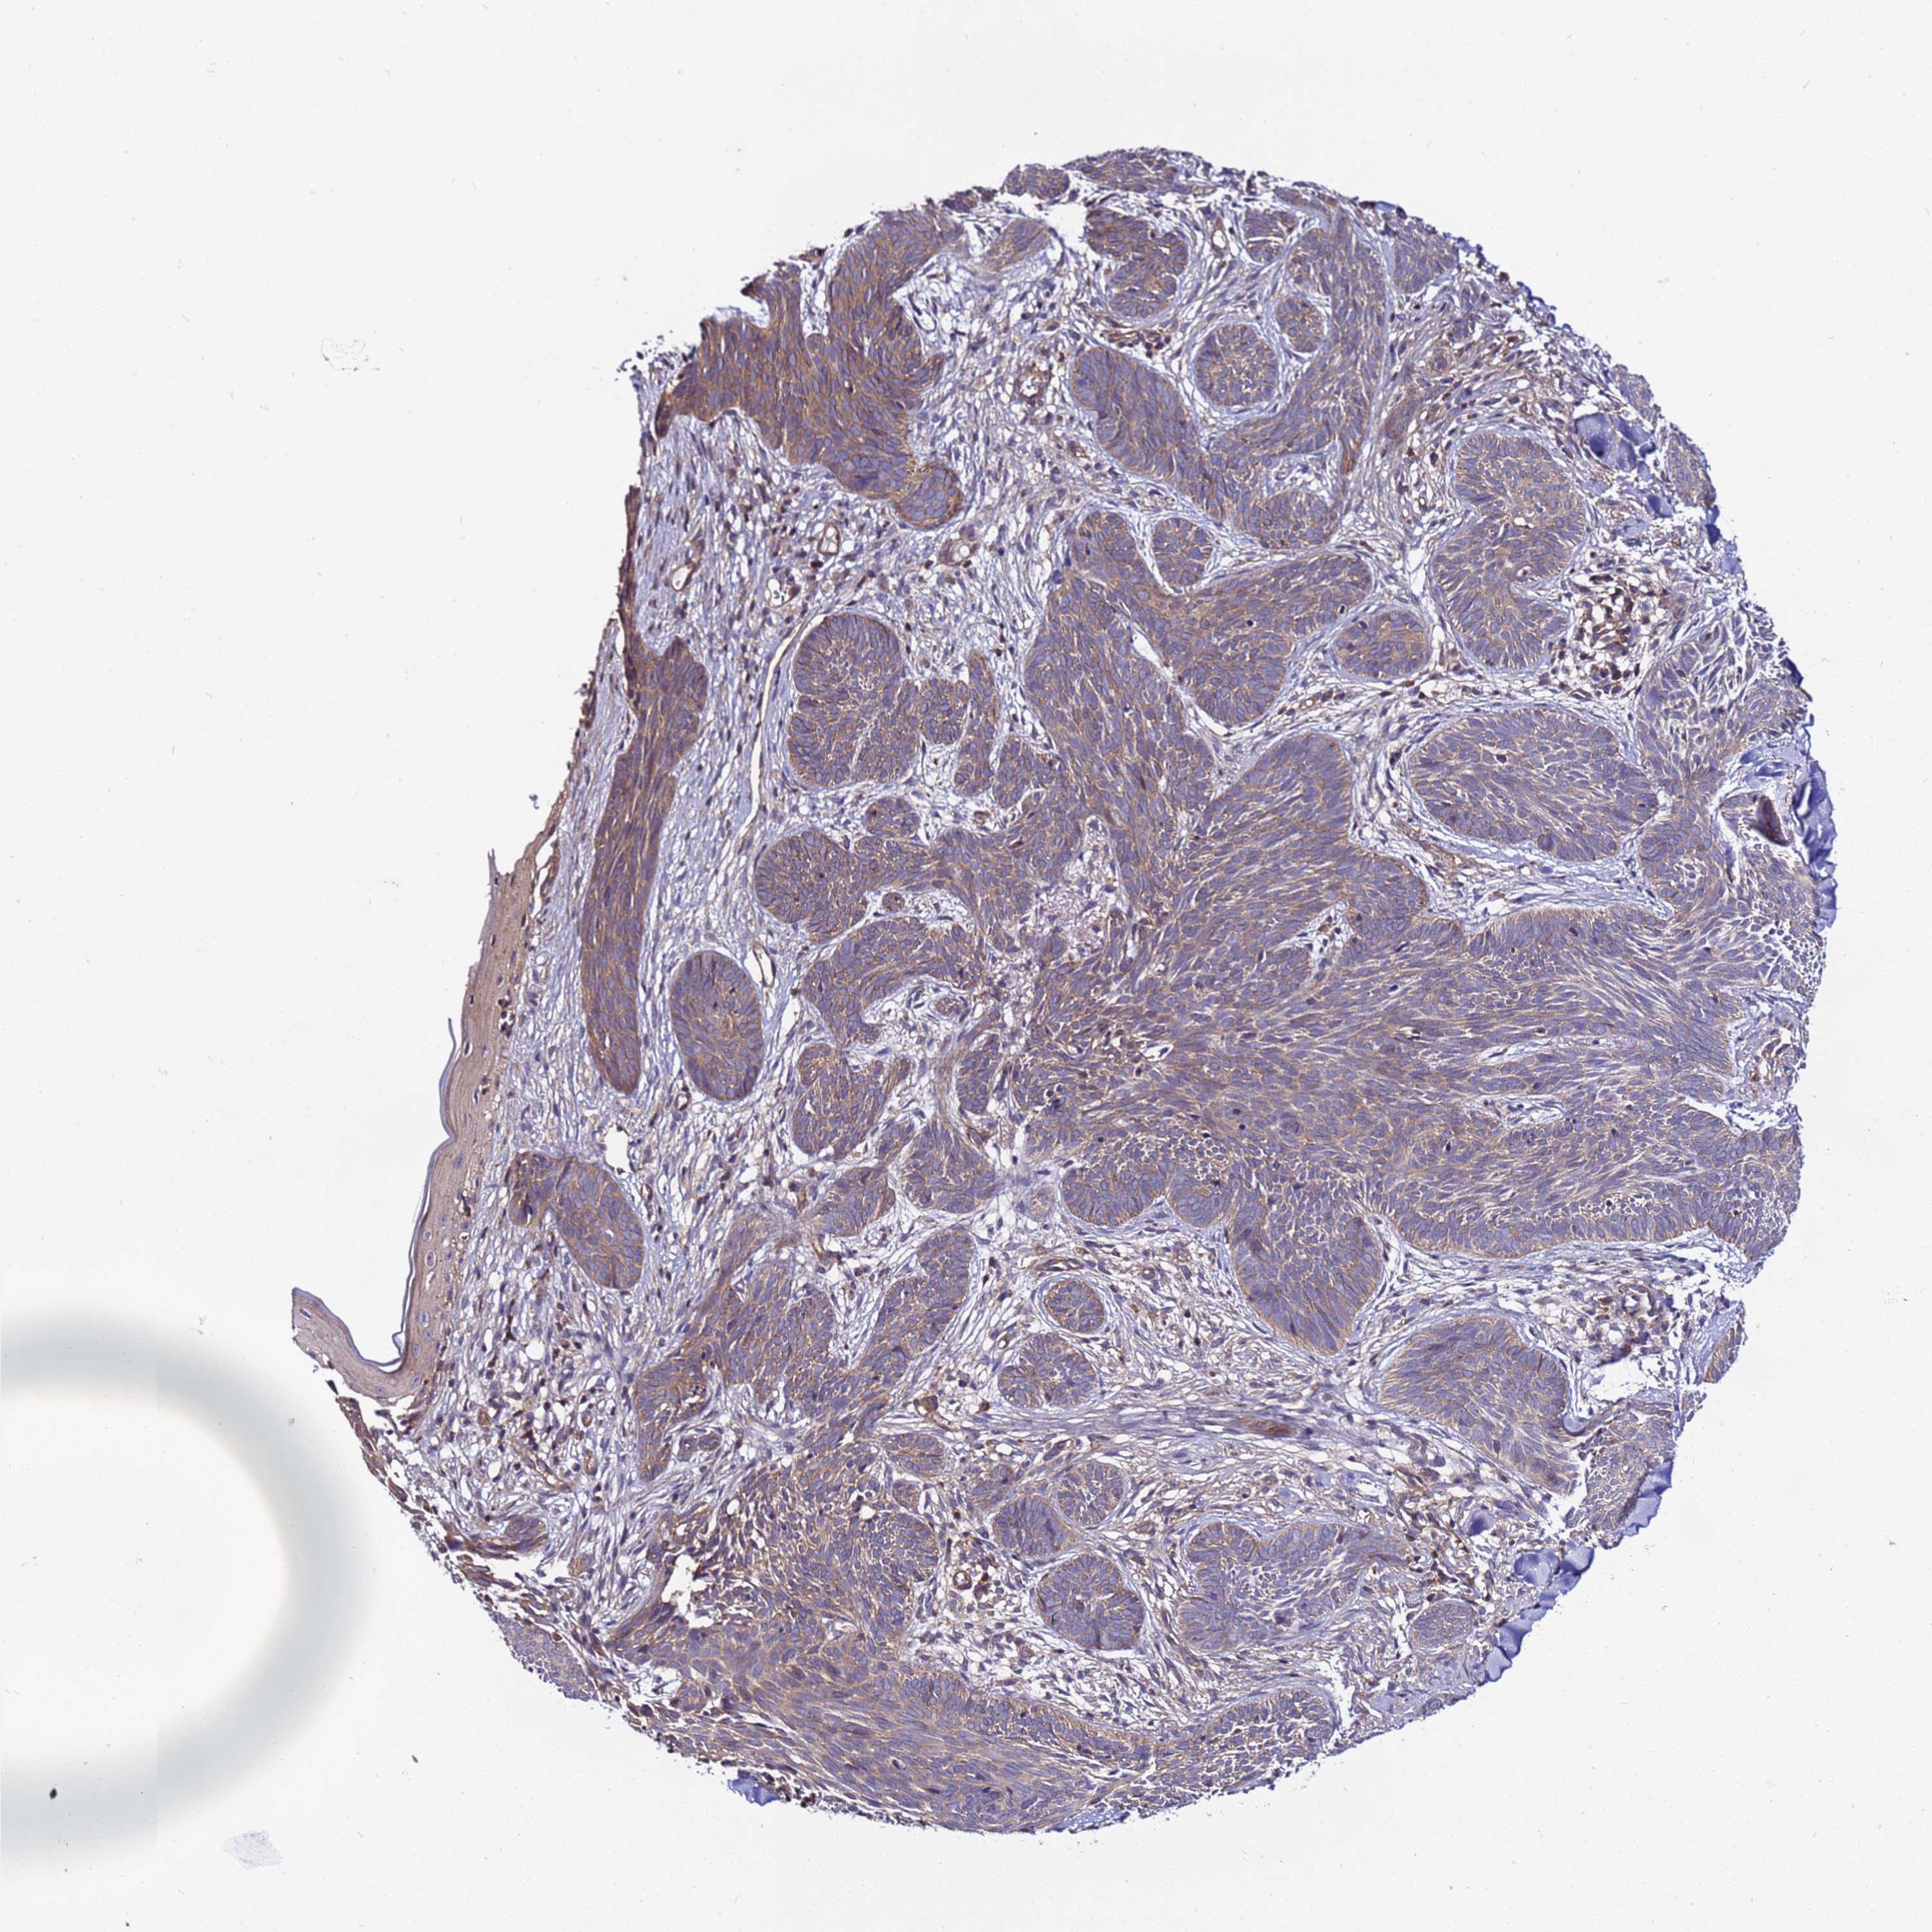

Squamous cell carcinoma, NOS

Squamous cell carcinoma, metastatic, NOS